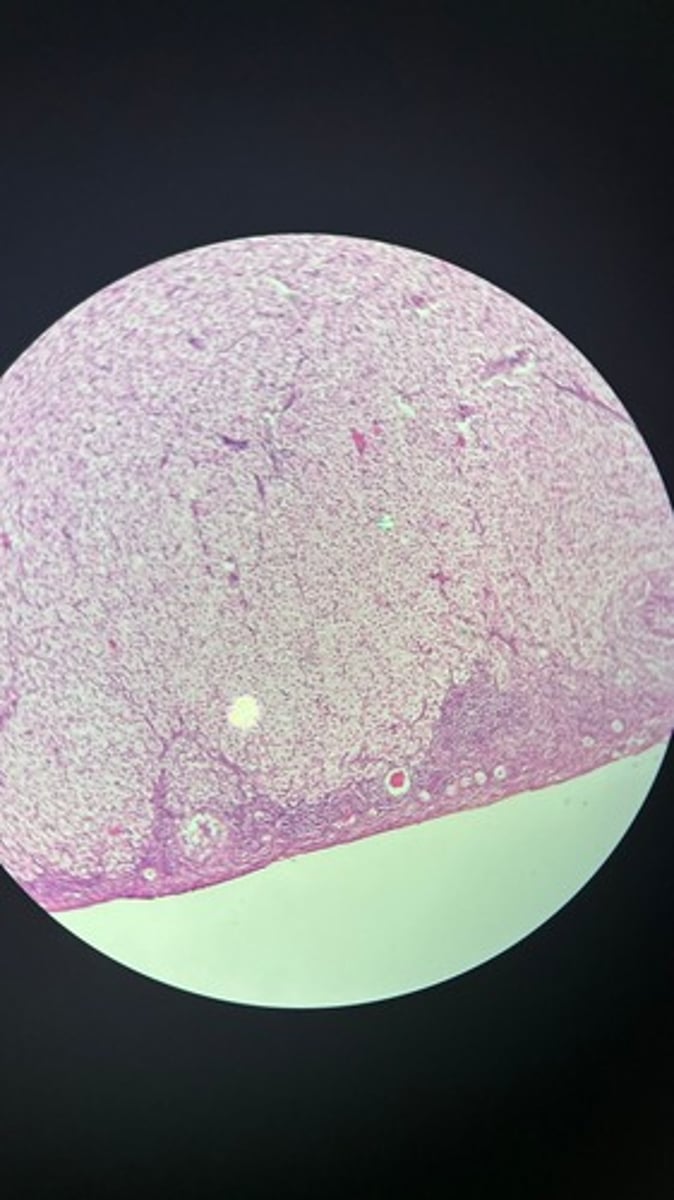

Spleen HE

Spleen HE

Spleen HE